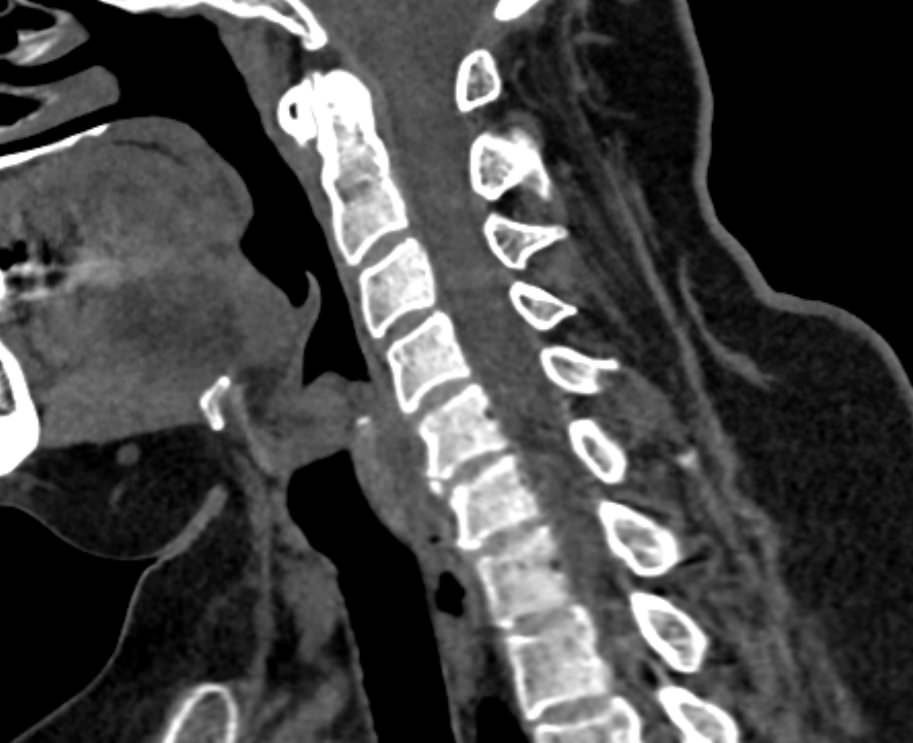

Мультиспиральная компьютерная томография (МСКТ) является современным, высокоинформативным методом диагностики различной патологии позвоночного столба. Благодаря МСКТ можно визуализировать костную структуру позвонков, выявить воспалительные, дегенеративные и опухолевые процессы на исследуемом уровне. В основе метода лежит использование ионизирующего излучения и способность различных тканей по-разному поглощать рентгеновские лучи.

В нашей клинике КТ двух отделов позвоночника проводится на новейших мультиспиральных томографах экспертного уровня TOSHIBA AQUILION (64-срезовый и 128-срезовый). Сканеры производят тончайшие срезы исследуемой зоны толщиной от 0,5 мм и позволяют визуализировать костные структуры позвоночника с высокой детализацией. Увеличенное количество высокочувствительных детекторов аппаратов обеспечивает высокую разрешающую способность и четкость изображений, при этом позволяет выполнить исследование в течение нескольких секунд с минимальной дозой облучения.

Инновационные возможности мультиспиральных томографов, которыми оснащены наши медицинские центры, позволяют создавать 3D-модели позвоночника на рассматриваемом уровне для более точной локализации очага и оценки взаимного расположения органов и тканей.